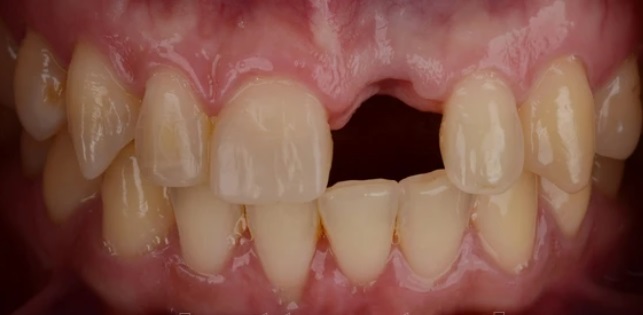

Проблема

Пациент обратился в клинику с проблемой отсутствия переднего зуба в следствии полученной травмы.

Решение

Пациенту проведено комплексное лечение по поводу восстановления переднего зуба при помощи имплантата Super Line и цельнокерамической коронки.